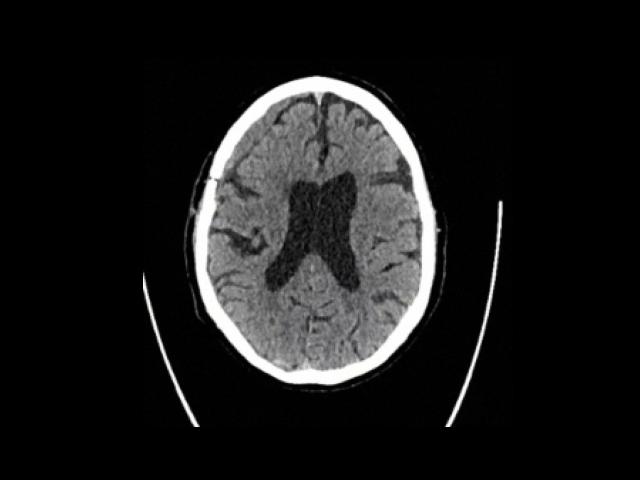

Sample Gallery